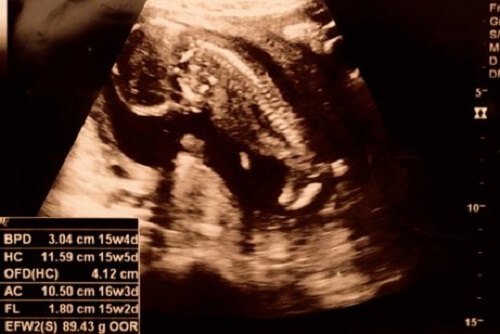

På noen ultralydbilder er det mulig å bestemme babyens kjønn allerede etter 15 uker. Videre vokser fosterets armer og ben og babyen kan bøye leddene.

I løpet av uke 15 har ikke skjelettet til babyen blitt ferdig ennå. Imidlertid kan du se ryggraden og nervene. Videre kan fosteret løfte nakken og hendene. I noen tilfeller kan du til og med se at babyen putter fingrene i munnen.